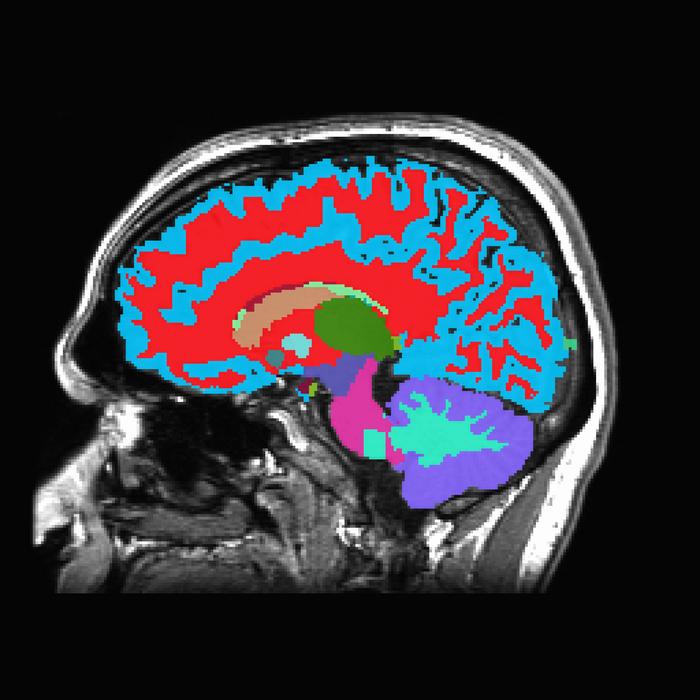

このツールは、1回のMRI脳スキャンから、中年期における慢性疾患のリスクを推定できます。通常、これらの病気は何十年も後になって現れるものです。この情報を知ることで、健康を改善するための生活習慣や食生活の変更への動機付けになるかもしれません。

DunedinPACNIと名付けられたこの新しいツールは、ダニーデン研究の参加者860人が45歳の時に収集された1回の脳MRIスキャンの情報のみを用いて、この老化ペースのスコアを推定するように訓練されました。

画像:あなたがまだそれなりに健康であるうちに、老化のスピードを測定するツールを想像してみてほしい。頭のMRIを撮るだけで、研究者はあなたの老化速度を測定し、認知症や身体障害のリスクを数年先まで予測することができる。